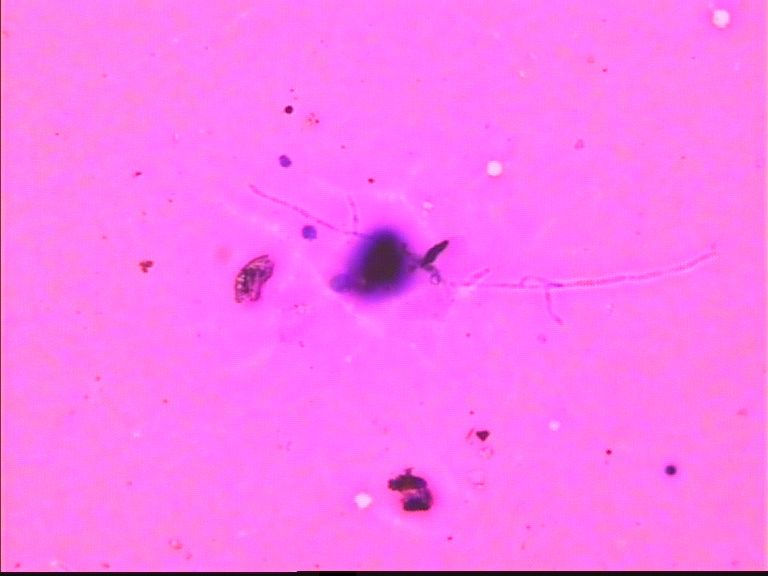

67岁胸水,有风湿病

• 67岁胸水,有风湿病图1

图1

没看出有设么异常细胞   图20好像有霉菌菌丝

深的可能是染料渣子

深染的东西像杂质

这些深染的是什么东西呢?好奇怪

制片质量欠佳,直接就看不出是什么了!

看不清,不能诊断

深染的不是细胞(就是细胞,看不到结构,也不能诊断)。